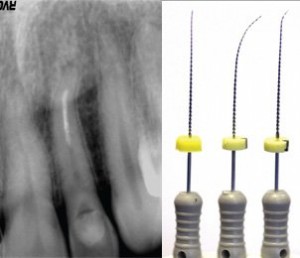

- Role of a pre-operative radiograph

- CASE DISCUSSION & ESTABLISHING DIAGNOSIS WITH RADIOGRAPHS